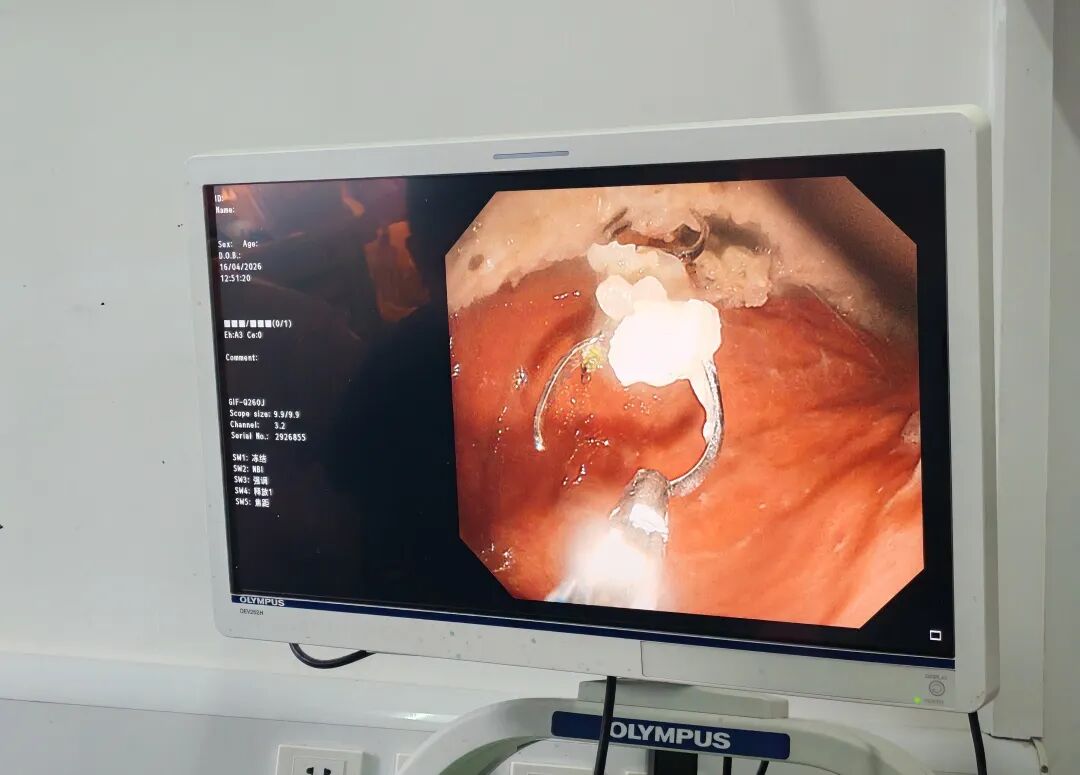

镜头三:精准锁定。用异物钳配合圈套器,医护协作,为防止划伤食管,两人反复尝试从不同角度先夹住假牙一侧,再慢慢往外一拖。

“往外退……慢……再慢……”

当假牙通过贲门时,所有人都捏了一把汗。那四枚金属爪紧贴着食管壁,稍有不慎就会造成损伤!

镜头四:成功取出!一路顺利通过贲门、食管,当假牙终于完整通过口腔、落在弯盘中的那一刻,清脆的“叮当”声响起,患者监护仪上所有数据正常。

“特工队”手法高超,全程仅用30分钟,假牙被成功“缉拿归案”,从嘴里完整取出。胃镜下,大叔的胃壁和食管仅有假牙脱落时造成的轻度划伤,无穿孔、无大出血。